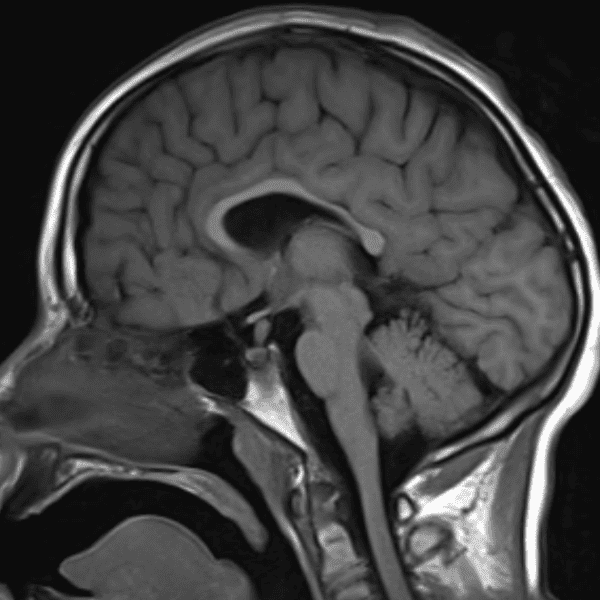

Classic Cases